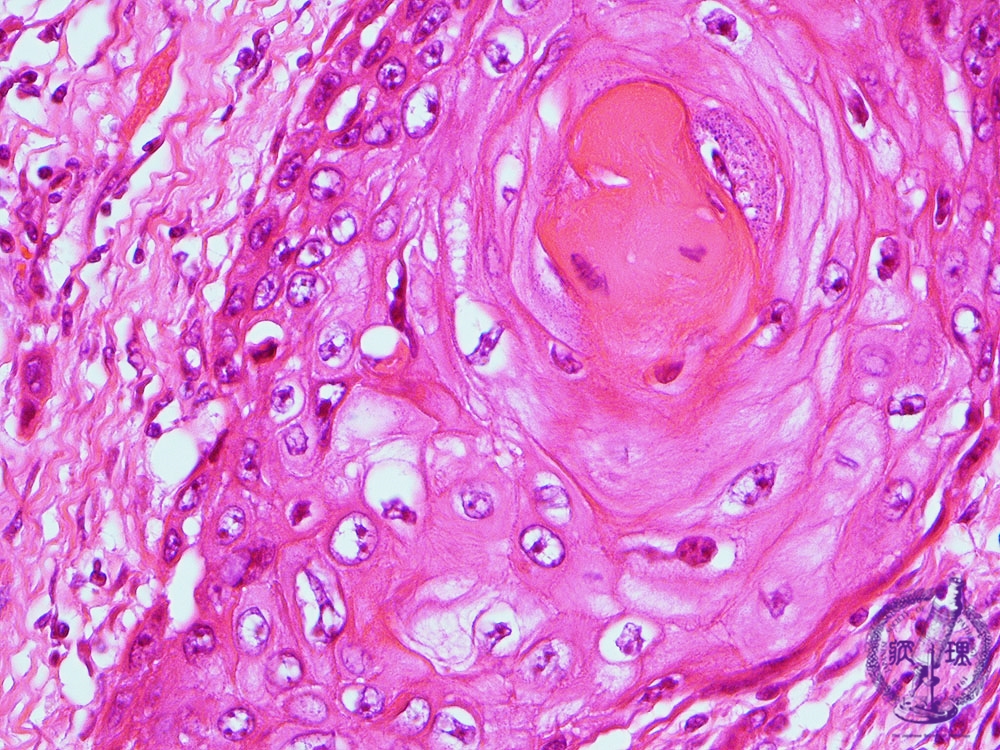

- š(5)Squamous cell carcinoma (larynx)

Microscopic view (high power view): Carcinoma cells have eosinophilic cytoplasm, compatible with keratinization. Structures with the appearance of a multi-layered onion like cross section are known as gkeratin pearlsh and are typical of keratinizing (squamous cell) carcinoma.